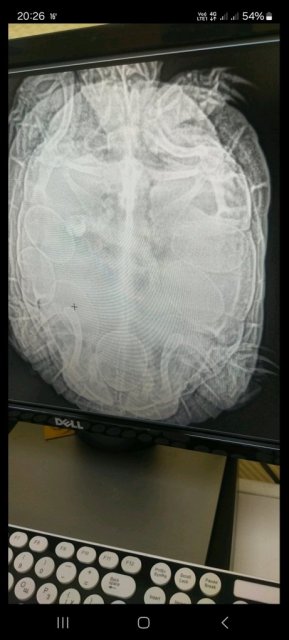

Спасибо за ответ! Уже показали, сделали рентген, 7 яиц, они давят на лёгкие из за этого тяжело дышать в воде. Сделали кальций, окситоцин и ещё что то. Черепаха без изменений. По рентгену яйцо около выхода. Читала, что после окситоцина кладка происходит в течении дня, уже день прошёл, ничего нет( Может ли это яйцо выйти само, или нужна  операция обязательно? Фото рентгена прикрепляю.

Screenshot_20240524_202648_Viber.jpg

31 июня ( 5 день после операции) были у врача, сделали снимок, врач сказал ничего особенного он там не видет, сказал продолжать лечение и ушёл в отпуск.